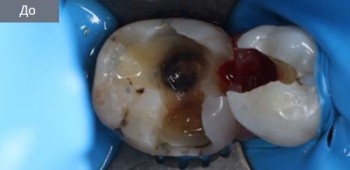

36 работ в портфолио